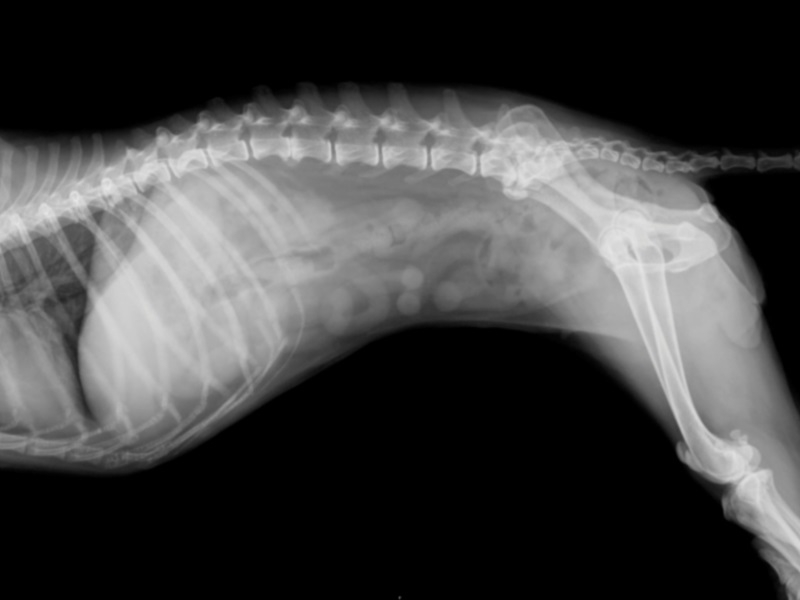

Диагноз ставится на основании рентгенографии и ультразвукового исследования, возможна серологическая диагностика (по типу антител, вырабатываемых к определенным разновидностям рака). Единственный шанс спасти животное – хирургическая операция. К сожалению, возможно ее осуществление далеко не в каждом случае.

В более тяжелых случаях отмечается ослабление или утрата безусловных рефлексов. Диагноз невозможно поставить без магнитно-резонансной томографии (MRI) или компьютерной томографии (CT), а также рентгена пораженных участков. При появлении неврологических признаков единственным способом лечения является оперативное вмешательство.